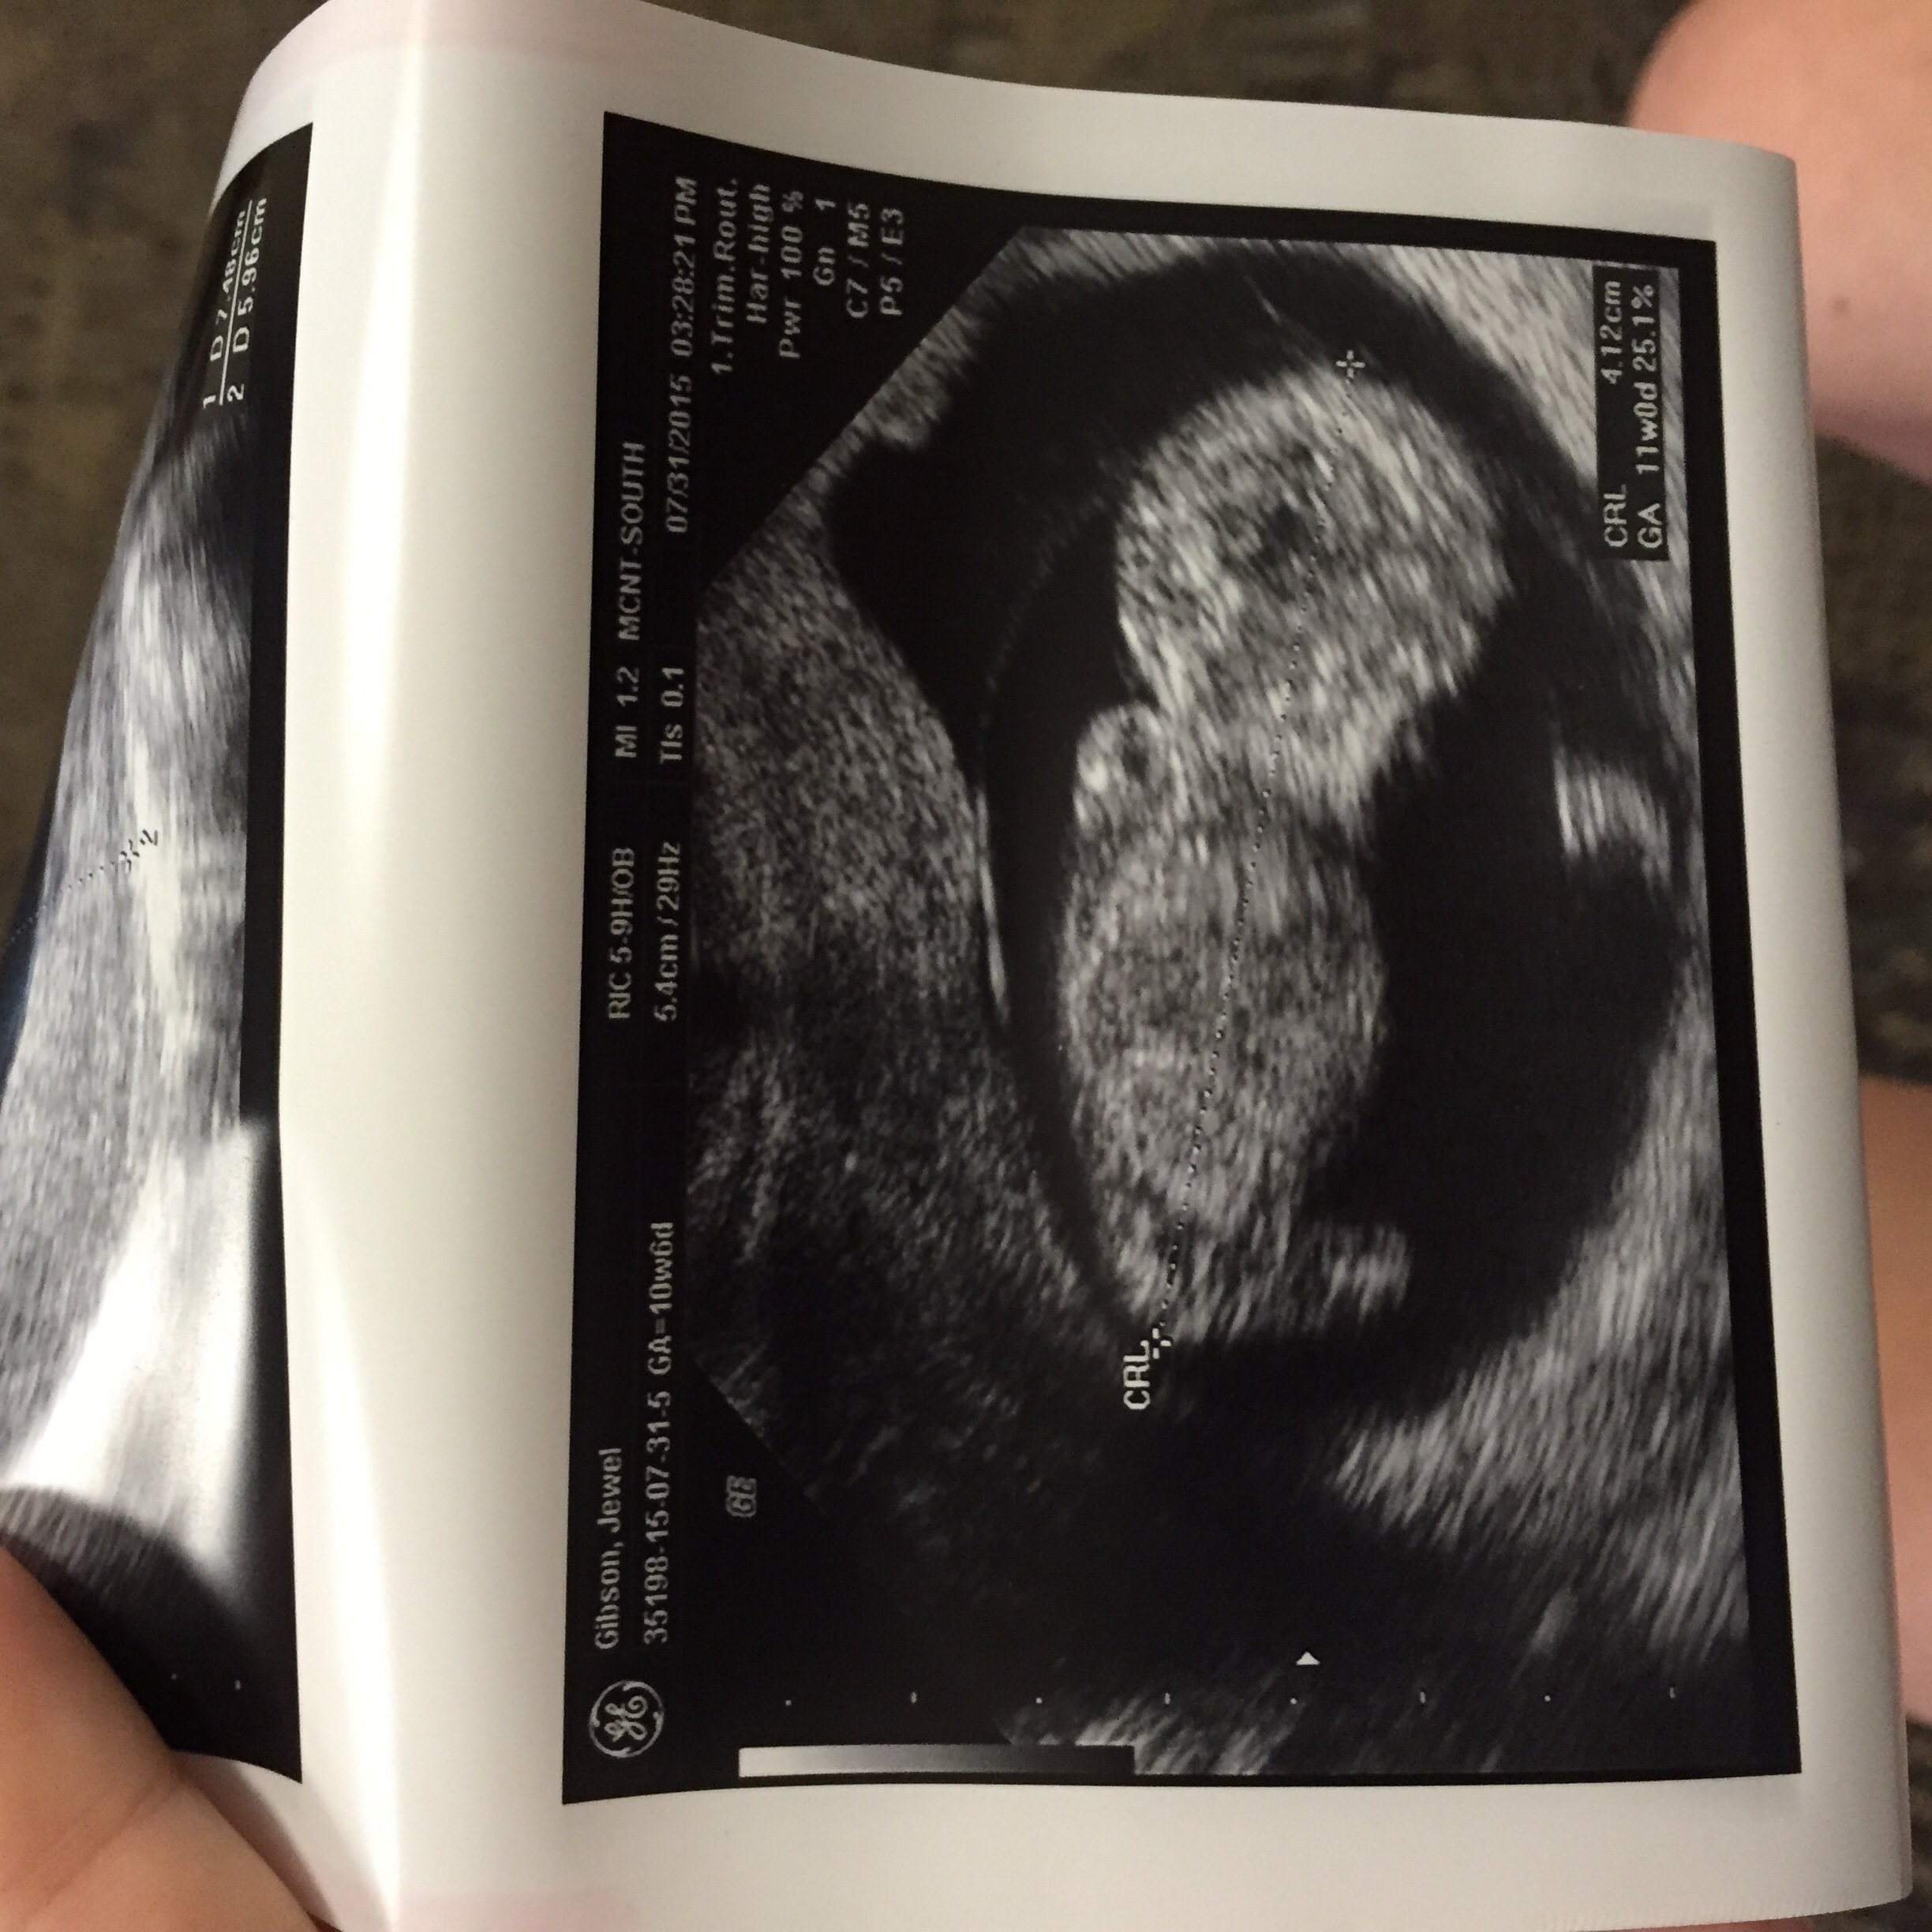

Went for 10wk check up today. Baby is right on schedule and her heart rate is 172 and decided to do a little dancing for the camera today. It was so amazing!